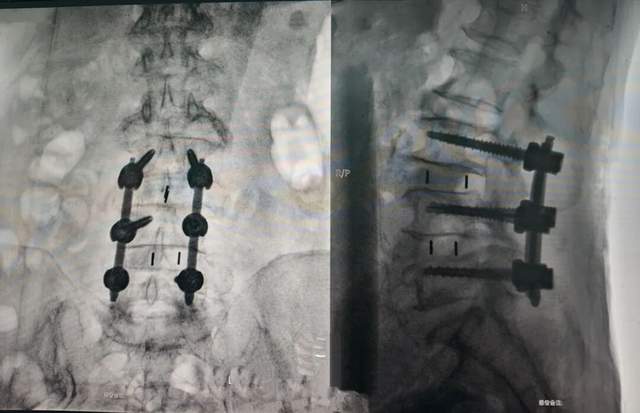

术后影像:

术前3D规划:基于CT数据,机器人提前计算椎弓根钉道,误差<0.5mm。

仅10mm切口:通过工作通道完成腰3/4、腰4/5椎间融合,神经根松解,解除神经压迫。

植入生物相容性融合器,恢复椎间隙高度。

手术历时2.5小时,出血仅200ml。